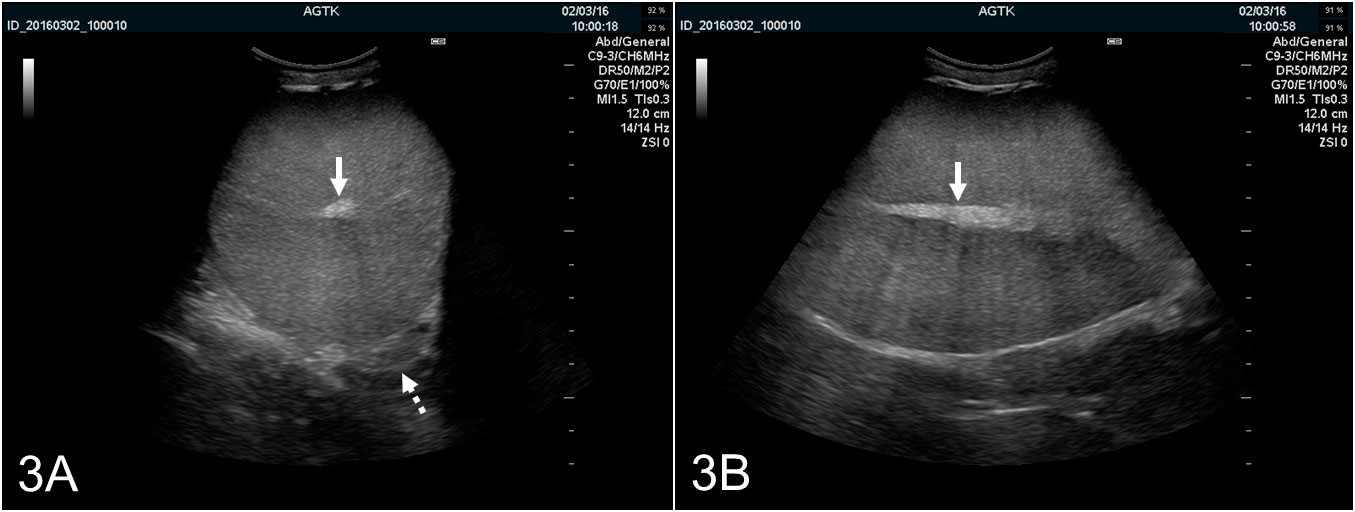

Les testicules peuvent être scannés longitudinalement ou transversalement (Figure 2A et B). Pour déterminer la circonférence testiculaire, des images transversales doivent être utilisées. Le tissu testiculaire sain a une échogénicité moyenne avec une échotexture homogène avec le rete testis hyperéchogène dans le centre du testicule (Figure 3A et B).